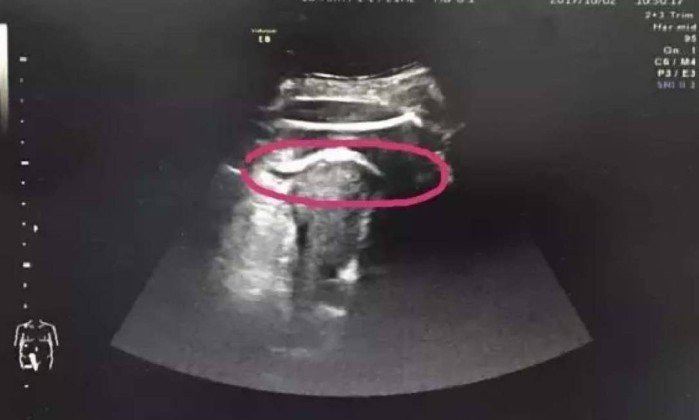

PEQUIM — Grávida de 35 semanas, a chinesa identificada como Zhang quase perdeu a vida e o bebê por um fato inusitado. No último dia 2, ela acordou com fortes dores abdominais e procurou o hospital. Após os exames iniciais, os médicos do Hospital da Universidade de Pequim, em Shenzhen, perceberam que ela apresentava alterações na pressão sanguínea, pulsação e respiração, levantando a suspeita de ruptura no útero. Uma ultrassonografia confirmou o diagnóstico, mas com um detalhe incomum: uma das pernas do bebê estava do lado de fora do órgão.

O procedimento era considerado de risco, pois Zhang sofria de forte hemorragia interna, mas a cirurgia correu normalmente, e a mãe e o bebê passam bem. Na operação, os médicos confirmaram que a perna do feto estava cutucando a cavidade abdominal da mãe, passando por um corte de sete centímetros no útero.

Durante a cirurgia os médicos encontraram um buraco de sete centímetros no órgão - Hospital da Universidade de Pequim